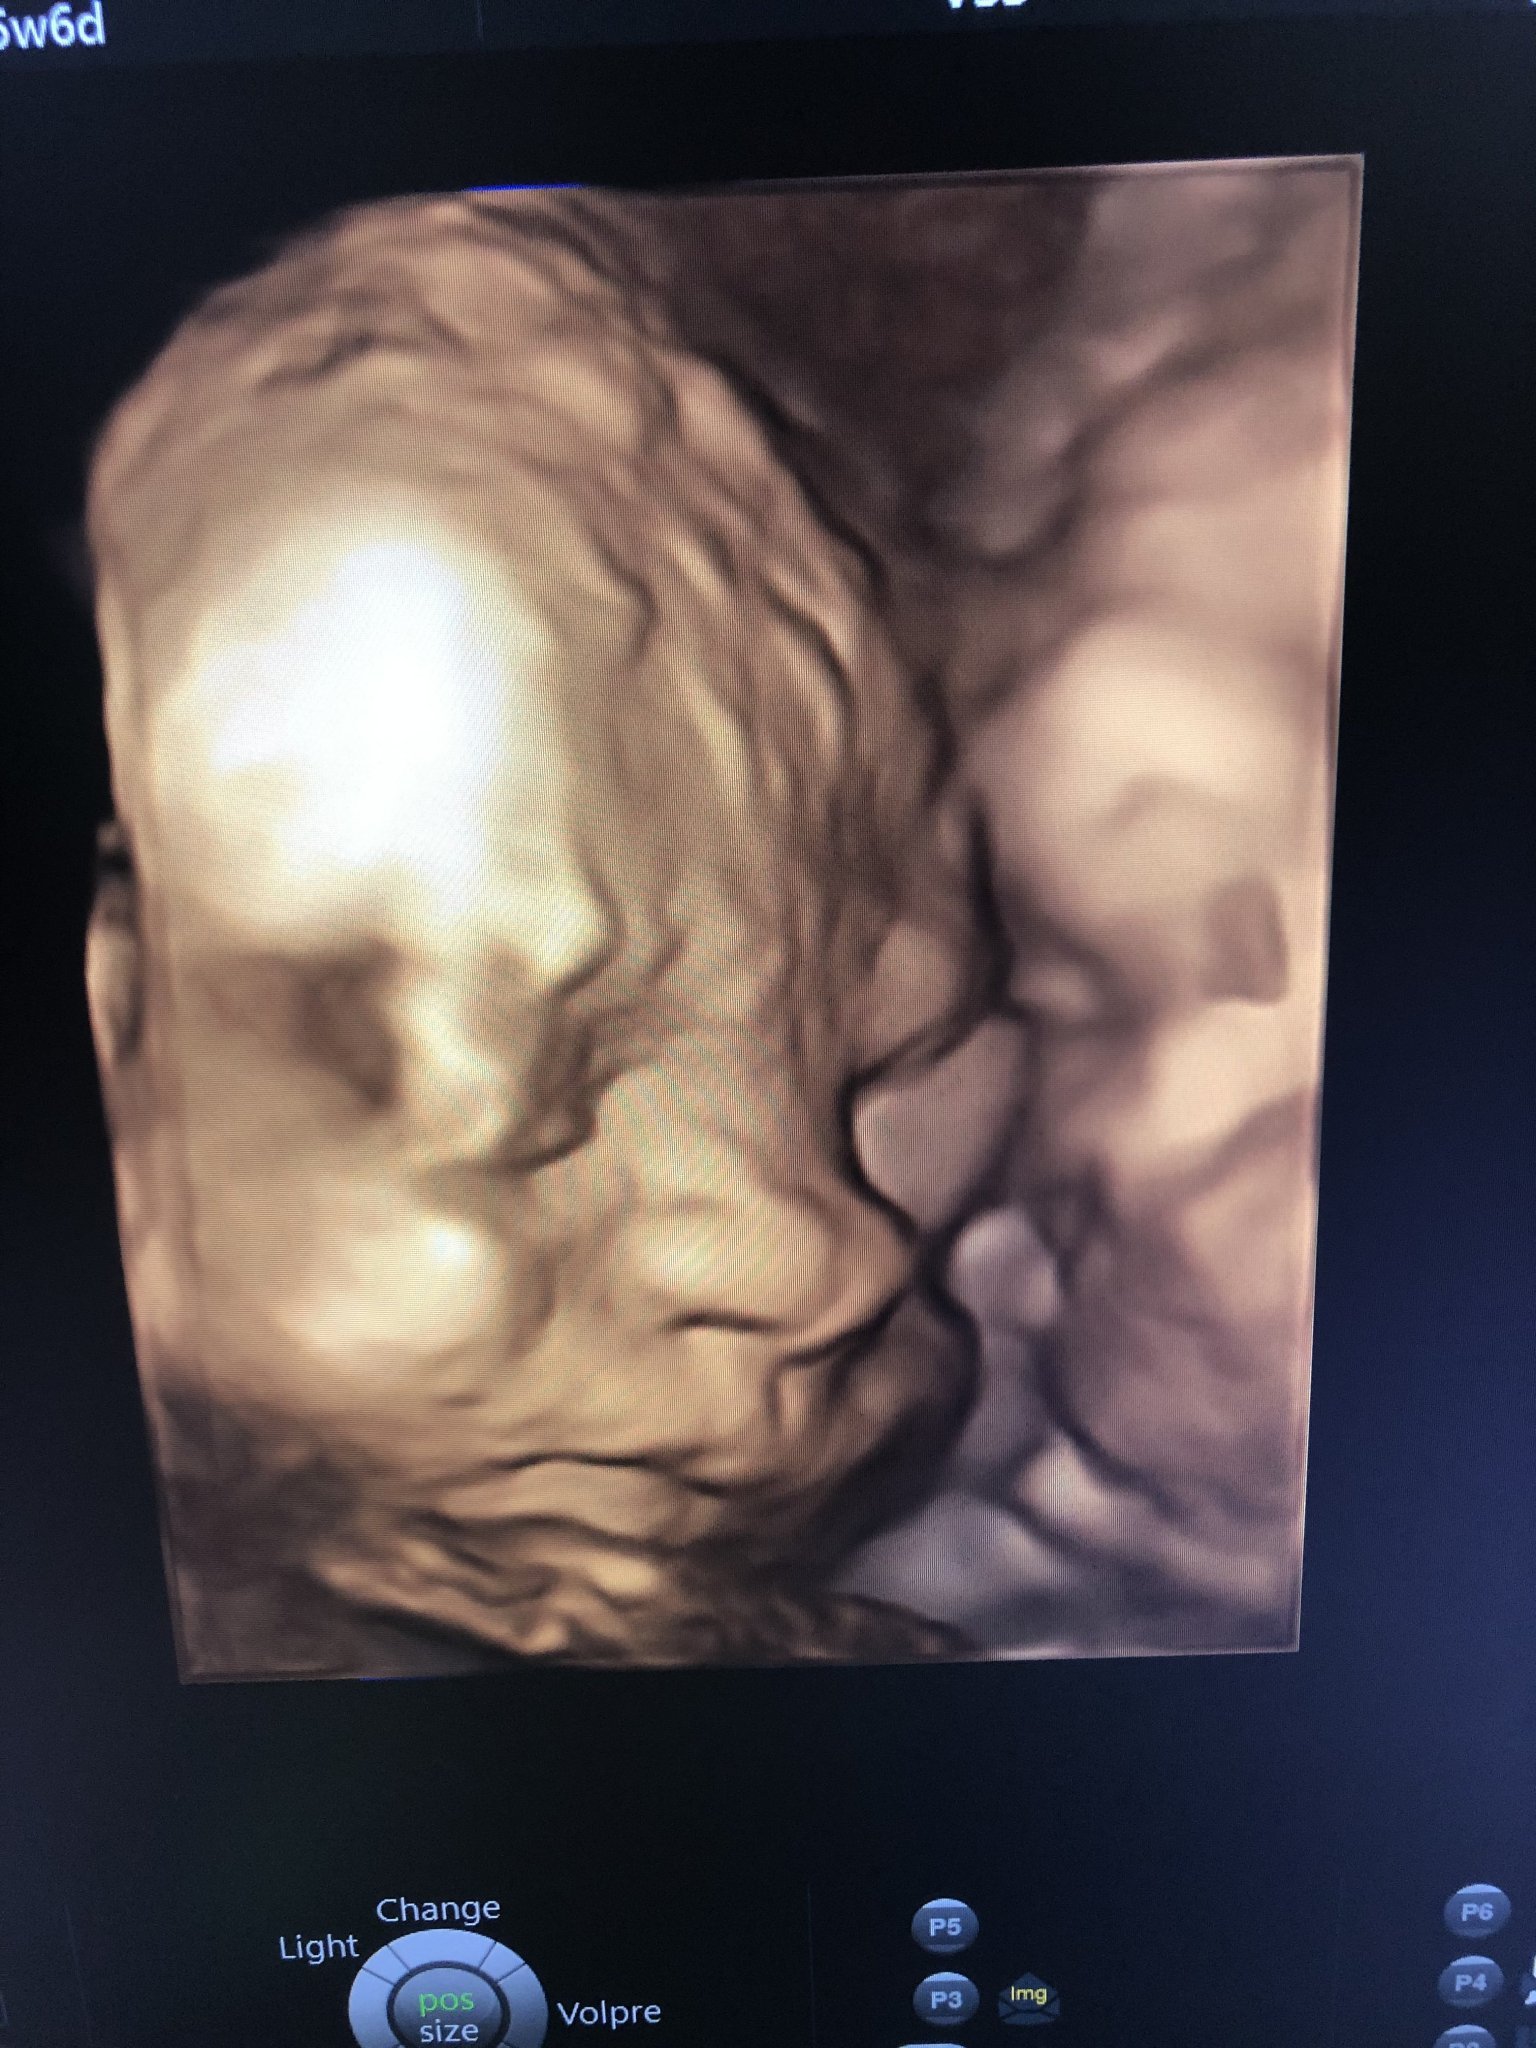

Аз вече съм в 26 г.с и бебокът е 870гр. ☺

Ходя редовно на контролни прегледи при д-р Атанасова, за да следим шийката, много е доволна от серклажа, направо му се радва всеки път като ме гледа, колко добре се е получило и че няма усложнения.

Шийката към момента е 36мм, а точно преди процедурата беше 28мм.